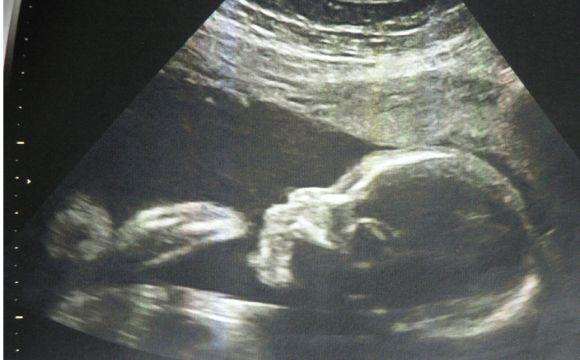

已经4个月大的宝宝,已经在肚子里活动了一百多天的孩子,就这么说再见,真的舍得吗?可是舍不得又能怎样呢?